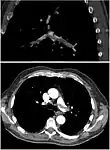

Segmental and subsegmental pulmonary emboli on both sides

CT pulmonary angiography showing a "saddle embolus" at the bifurcation of the main pulmonary artery and thrombus burden in the lobar arteries on both sides.